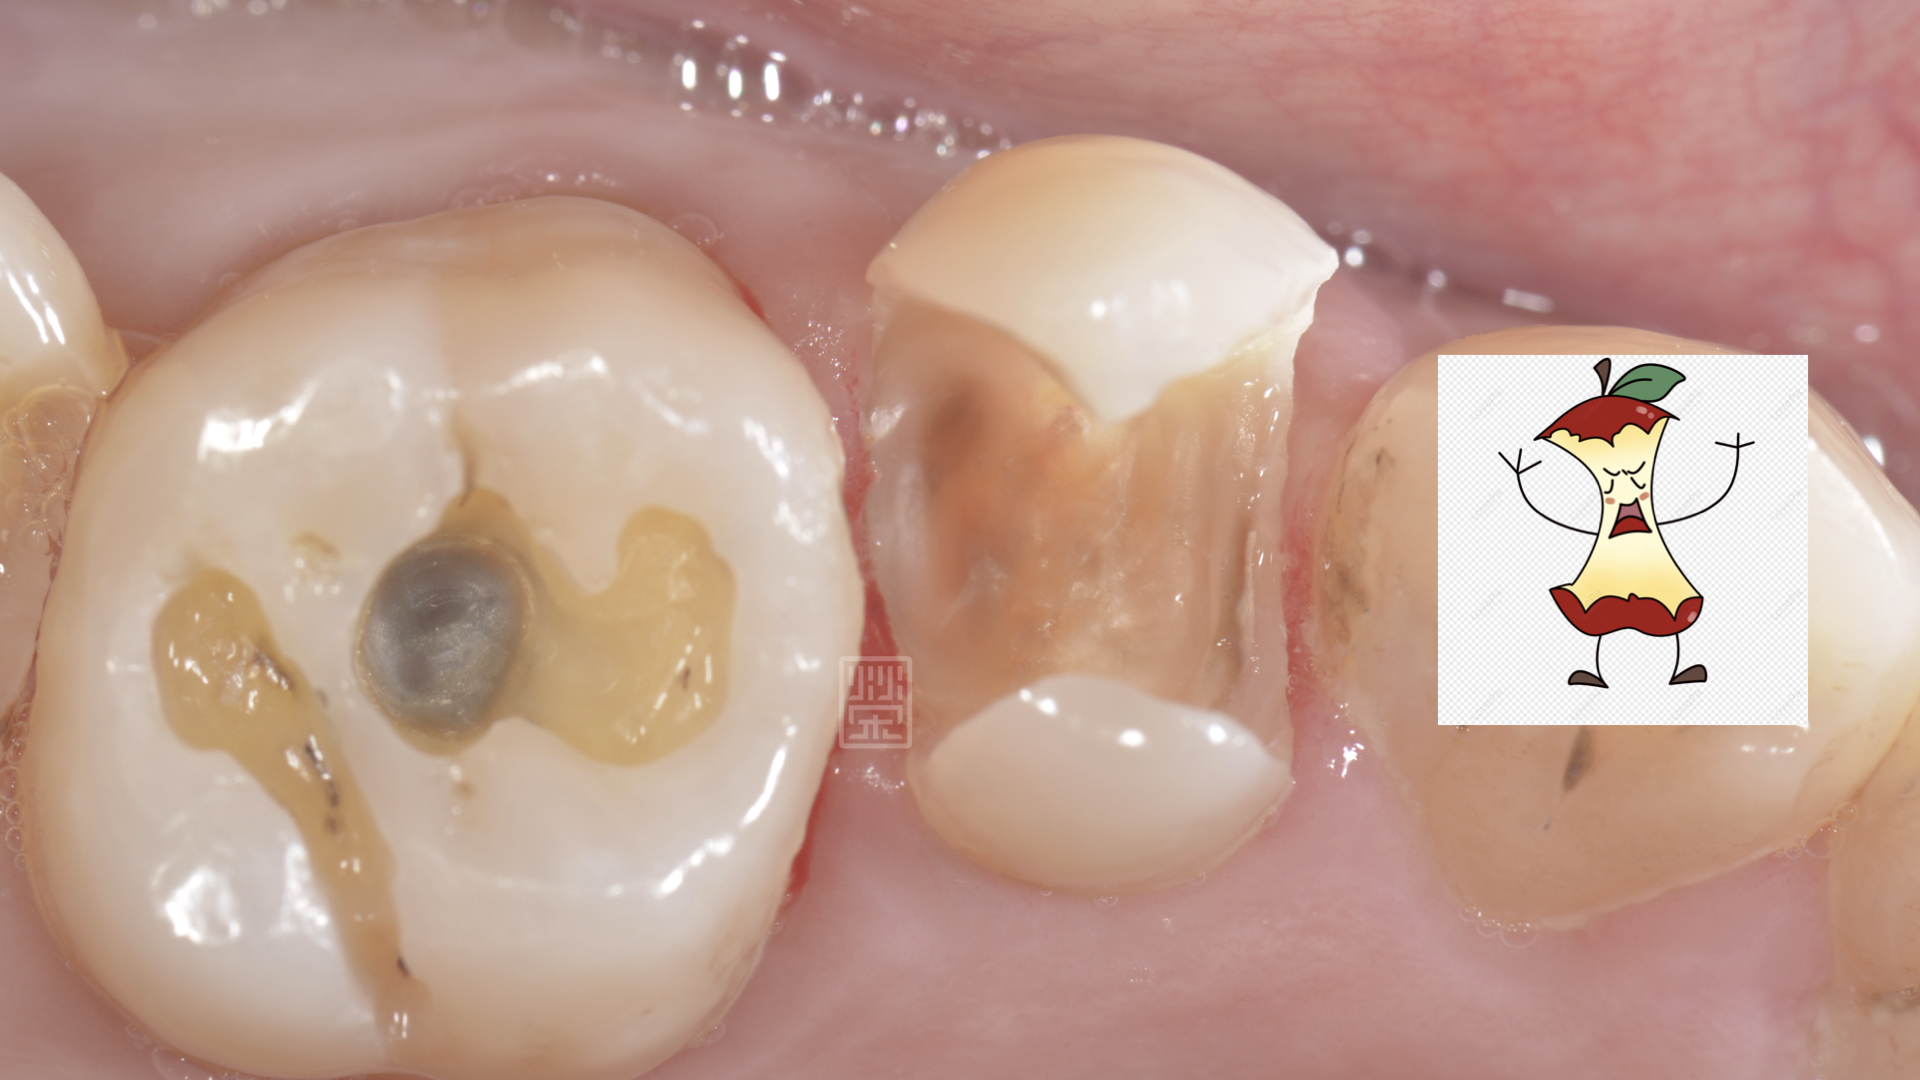

將舊填補物與蛀牙清除後,剩下兩片薄薄的齒質,看上去就像是卡通蘋果被咬一圈,首先先考量牙髓神經的健康性,X光與臨床檢查上,牙髓仍是健康的狀態,但是剩餘健康的齒質這麼少,要怎麼恢復牙齒的強度呢?

蛀牙拿乾淨後,很像蘋果卡通圖被啃一圈的樣子